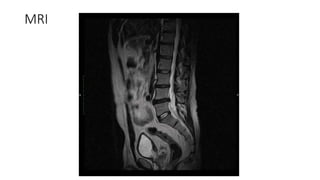

• MRI

MRI